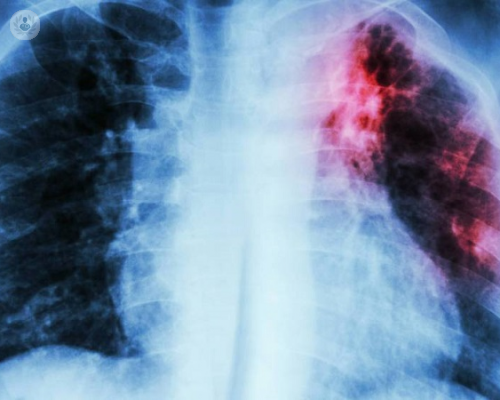

Fibrosis Pulmonar Idiopática: mejorando la respiración, mejorando la vida

Se caracteriza por la formación de cicatrices (Fibrosis) en el tejido pulmonar, lo que dificulta la respiración y reduce la capacidad de los pulmones para funcionar correctamente.